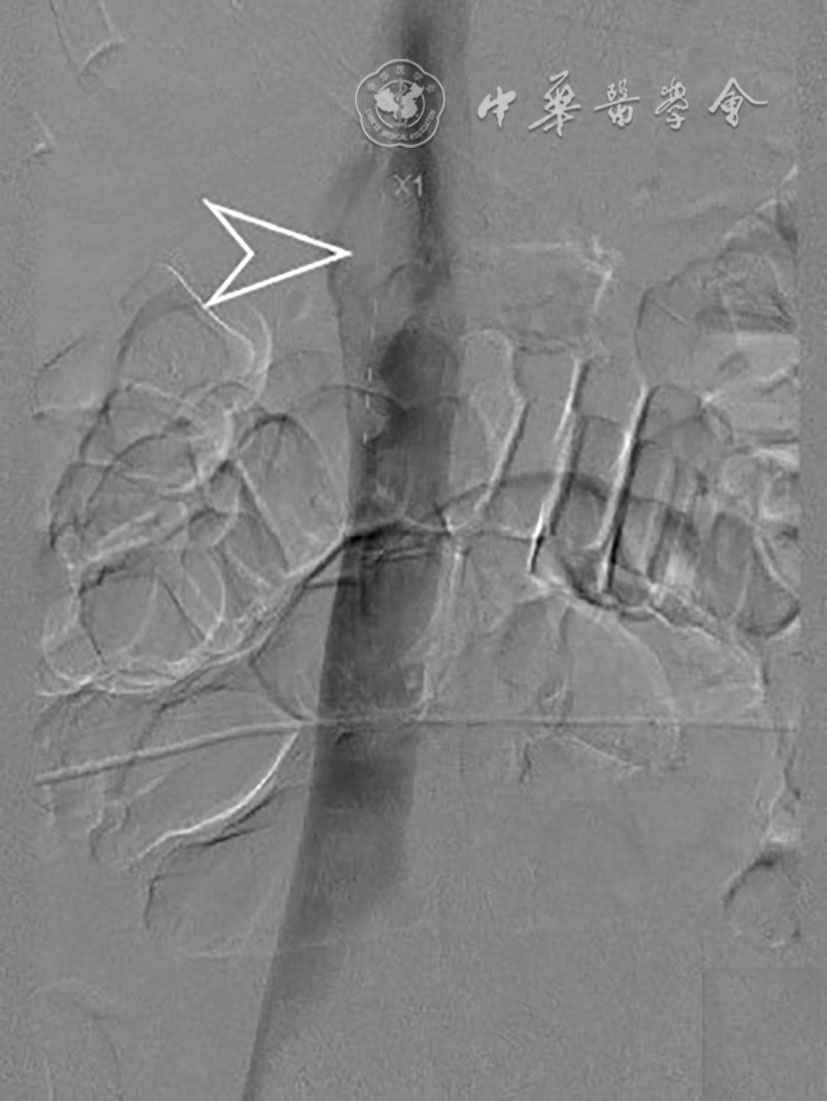

Tao Chen, Hongjian Shi, Liang Zhou, Zhen Gan.

Interventional treatment for delayed postoperative hemorrhage after gastric and pancreatic-biliary surgery

[J]. Chinese Journal of Interventional Radiology(Electronic Edition), 2024, 12(01): 39-44.